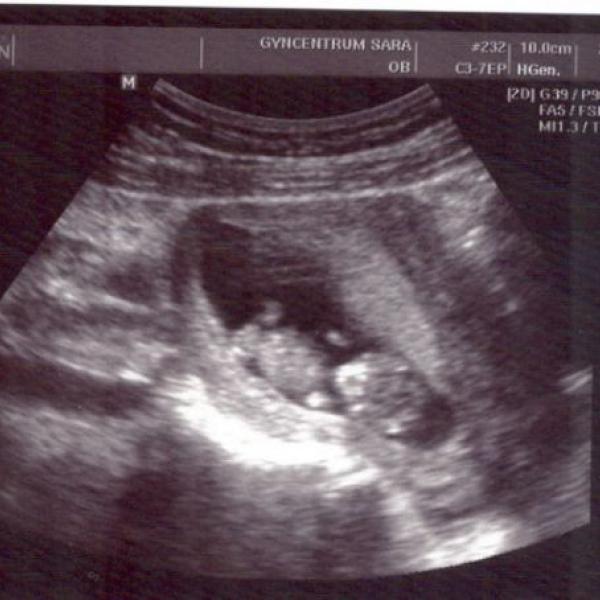

Ahojky :€O: ... tak tady je naše první fotečka :))) krásný den všem :k: :!k:

Milé těhulky ...tak jsem včera byla na kontrole v týdnu 9+0... miminku se daří dobře, bylo krásný ho zase vidět, jak už má krásně viditelné nožičky, ručičky.